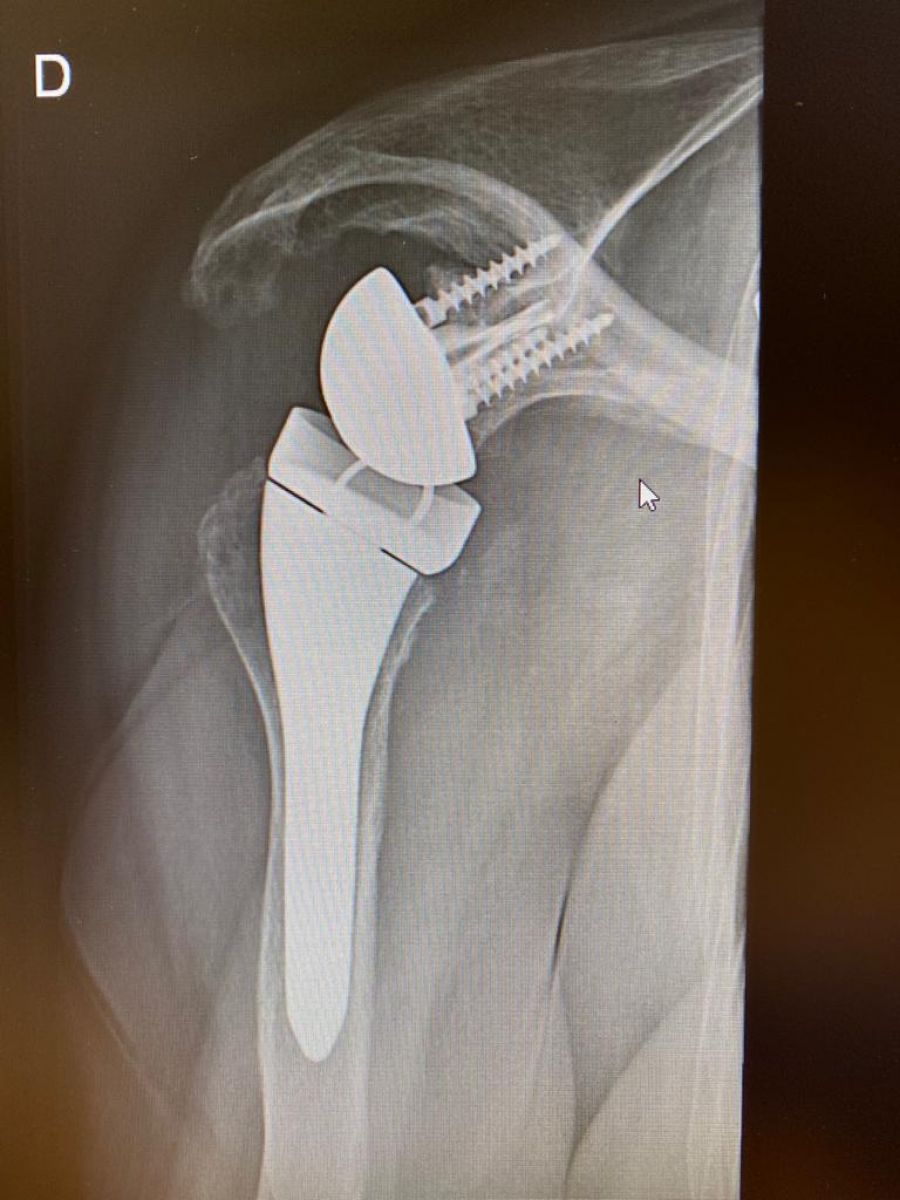

S-a specializat în chirurgia membrelor superioare la Centre Hospitalier Universitaire de Strasbourg, unde a aprofundat chirurgia specifică a cotului și umărului.

Dotați cu două camere amplasate pe rame, ochelarii HoloLens permit atât filmarea unui pacient în timp real, cât și reproducerea scheletului folosind o hologramă, totul de la distanță. Această proiecție tridimensională se potrivește direct în câmpul vizual al utilizatorului. Iar botoșăneanul Jean Ciornohac a efectuat deja două operații de succes cu dispozitivul inovator, astfel ajungând să reprezinte Belgia la amintitul eveniment.

”Astăzi avem posibilitatea de a reuni virtualul cu lumea operațională. Scopul operației este de a putea standardiza procedurile chirurgicale. Setul cu cască îmi permite, de asemenea, să explic pacientului operația mea și să reduc erorile medicale, erorile umane Este minunat să aducem această tehnologie în sala de operație și să putem reconstrui o articulație care este distrusă”,